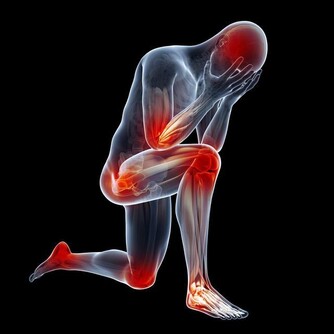

西醫認為,手腳麻木是痺栓引起的。“痺栓”,沉積在神經通路里,是神經細胞代謝物、神經毒素相互吸附粘合而成,就像電線中間有段橡皮膠,使生物電流無法通過,病人感覺手腳麻木。

事實的確如此。老人癱瘓之前就一直嘮叨:手腳發麻,胳膊抬不起,手握不住東西,連上廁所提褲子都費勁。哪裡知道,就在老人癱瘓前兩個月,體內痺栓急劇上升,老人身體不斷發出不祥信號:抽筋,手指就像木頭一樣,什麼感覺都沒有,並且疼痛加重。如果老人這個時候吃點清洗痺栓的藥,就不會癱在床上。遺憾的是,兒女們沒有把它當回事,才造成今天的結果。有些病人會出現“無痛”心髒病,其最關鍵的前兆是:突發暈眩、心跳加劇、氣短、噁心、嘔吐、冒冷汗。如果身體出現上述某些症狀,要第一時間打120急救。病人口中可含一片阿司匹林或硝酸甘油,以防心髒病發作時心肌受到損傷。

腿肚子酸痛、胸痛、氣短、咳血。這些是危險的腿部血栓形成前兆。久坐之後最易發生,手術之後長時間臥床,也會出現這種症狀。人人都可能得這種病,坐臥時間久了,血液淤積在腿部,腿部出現血栓,小腿肚子腫疼,此時如果突然出現胸痛或者氣短,說明血栓可能已經脫落並通過血液進入肺部。那可是萬分危險,要立刻去醫院。